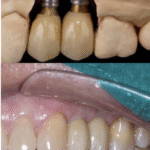

ที่คลินิกทันตกรรมไวซ์ เรามีทีมทันตแพทย์เฉพาะทางรากฟันเทียม (Implantologist) ที่มีประสบการณ์สูง พร้อมอุปกรณ์และเทคโนโลยีที่ทันสมัย เพื่อให้การรักษามีความแม่นยำ ปลอดภัย และอยู่ได้นาน

ด้วยเทคโนโลยีที่ทันสมัยของทางคลินิก ทำให้การผ่าตัดในเคสทั่วๆไป มีแผลเล็ก ปวด บวมน้อยมาก พักฟื้นเร็ว แทบไม่แตกต่างกับการถอนฟันทั่วไป

รากฟันเทียมเป็นฟันปลอมที่อยู่ได้นานที่สุด ถ้าดูแลสุขภาพช่องปากได้ดี และมาตรวจติดตามทุก 6 เดือน รากฟันเทียมจะอยู่ได้เฉลี่ย 15–20 ปี ที่สำคัญคลินิกมีการรับประกันตัวรากเทียมและครอบรากเทียมอีกด้วย